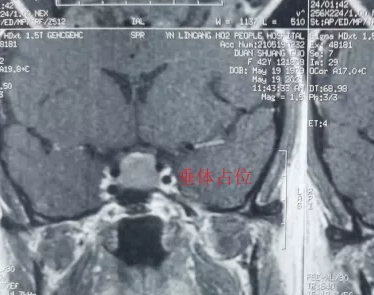

患者段女士,42歲。反復頭暈、眼花、心慌已經5月多了,5月前當地醫院頭顱CT未見明顯異常。1周前患者頭暈、眼花越發嚴重,輾轉多個醫院無果后,患者來到我院內科住院檢查,完善頭顱CT后,發現鞍區占位,考慮垂體腺瘤可能。

當外一科楊金雷主任到達內科時,已經找不到段女士的身影了。楊主任通過查看患者病歷,電腦閱讀CT,診斷患者為垂體腺瘤并出血可能,即患者可能存在瘤卒中。要求立刻打電話讓患者返回醫院接受正規系統的治療。

5個月的時間,CT結果提示鞍區占位病變,進行性增大,考慮瘤卒中可能。

完善檢查后,段女士被確診為無功能性垂體腺瘤并卒中。通過積極術前準備,楊金雷主任帶領的外一科醫護團隊,在省級專家指導及我院麻醉手術室的精誠協作下,為段女士開展了顯微鏡下經鼻蝶垂體腺瘤切除術。手術歷時1.5小時后順利結束。